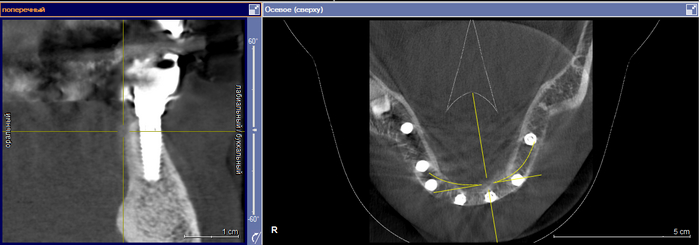

Устройство Dimoveo помещается на колено, а наночастицы, содержащиеся в физиологическом растворе, вводятся в место операции (Фото: предоставлено)

Запатентованное решение компании Dimoveo заключается в частичном повторном открытии хирургического участка и заполнении области физиологическим раствором, содержащим наночастицы железа. Затем наночастицы подвергаются воздействию ультразвуковых волн, заставляя их вращаться на высокой скорости, чтобы разрушить биопленку и дать возможность лечить инфекцию антибиотиками.

Димовео пока сосредоточен на имплантатах колена. Но Рамот говорит, что процедура подходит для любого вида замены суставов, например, колена, бедра, лодыжки, плеча и позвоночника, а также переломов костей, требующих установки винтов или пластины.